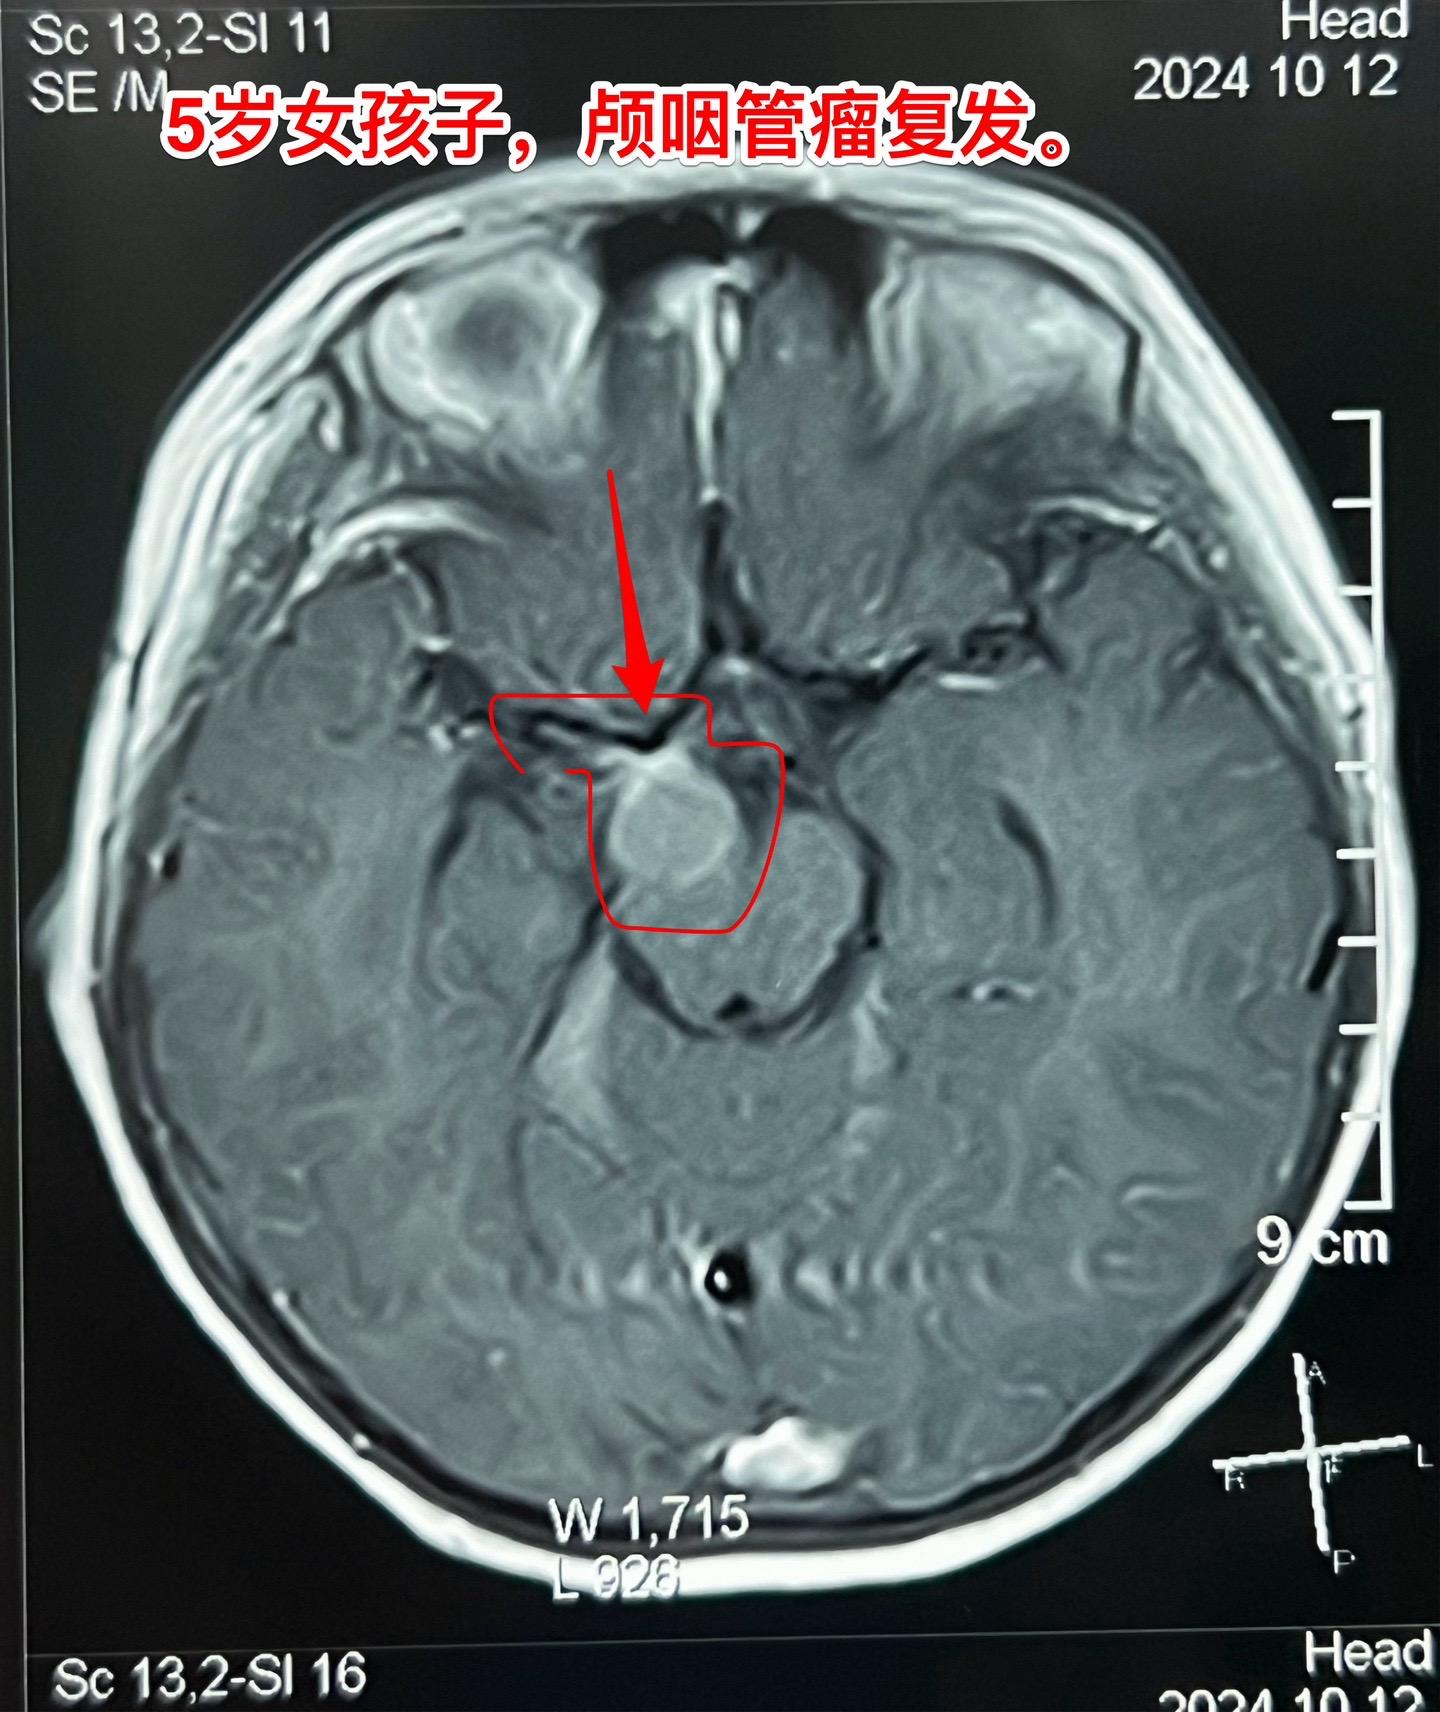

复发颅咽管瘤的手术难度好判断吗?5岁广州的女孩子,颅咽管瘤复发了。第一次手术在广州市某医院作的。现有的CT和磁共振显示肿瘤是一个囊,体积也不大。 这样的复发颅咽管瘤手术难度大吗? 一眼看上去,这个颅咽管瘤切除的难度似乎不大。但是在手术过程中发现,肿瘤与周围组织粘连紧密,分离过程很是艰难。 另外还有一个更难的难题,那就是这个肿瘤周围及其它位置有很多个散在的细小钙化斑。术中所见的钙化及肿瘤虽然切除了,术野之外的地方是不是还潜藏着钙化呢? 所以,复发